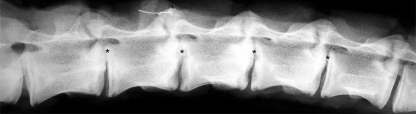

Regardless of age all sheep showed radiographic evidence of discitis in all inoculated discs from 2 weeks (Fig. 2). After 12 weeks erosive lesions were present macroscopically in all inoculated discs (Fig. 3). Microscopic changes consistent with discitis with additional haemorrhagic encapsulated granulation tissue response surrounding necrotic debris was observed in all control and treated sheep. Approximately half of the lesions breached the epiphysial growth plate (Fig. 4). The histological appearance was the same with or without antibiotic treatment.

Fig. 2.

Radiograph taken 2 weeks after four level disc inoculation of S. aureus. Discitis is evident in all inoculated discs (asterisk) demonstrated by endplate erosion and disc thinning comparable to adjacent non-inoculated levels